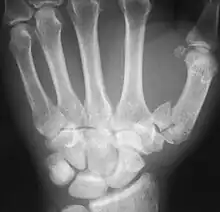

| Complete break at base of thumb | |

The Rolando fracture is a type of broken finger involving the base of the thumb.[1]

It is an intra-articular fracture.[2]

It was first described in 1910 by Silvio Rolando.[3] It is typically T- or Y-shaped.[4]